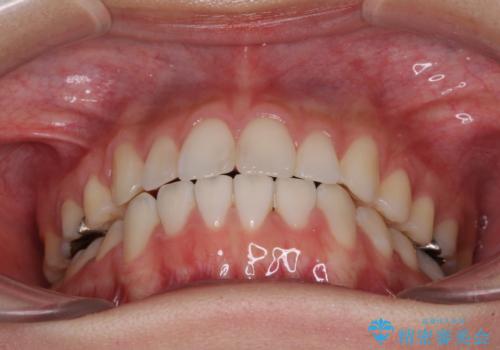

- 上下の八重歯を気にして来院された患者様です。

上下ともに八重歯の後ろの歯を1歯ずつ抜歯し、補助装置(リンガルアーチ)を用いて八重歯の位置を改善し、その後インビザラインにより矯正治療を行うこととしました。

途中海外留学をされたため、治療期間は長くなりましたが、事前に補助装置やワイヤー装置を併用したことで、きれいな歯列に仕上げることができました。